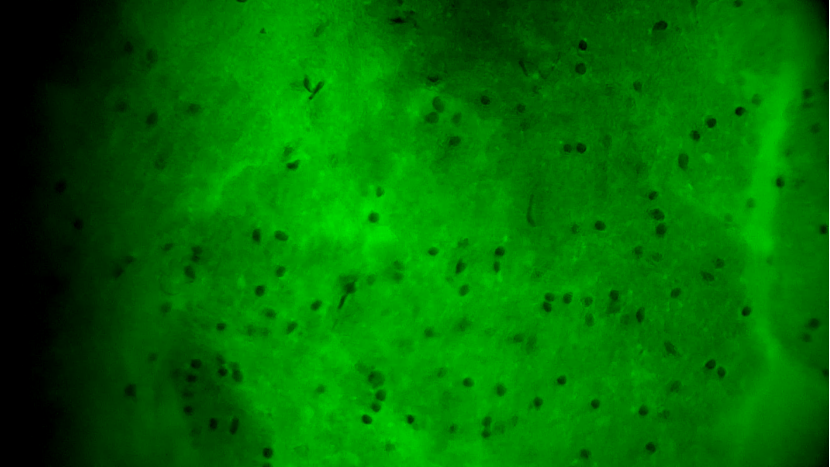

術(shù)中EndoSCell?細(xì)胞圖像如下:

腫瘤中心區(qū)域:細(xì)胞核異型性顯著,分布密集且不規(guī)則,陽(yáng)性。